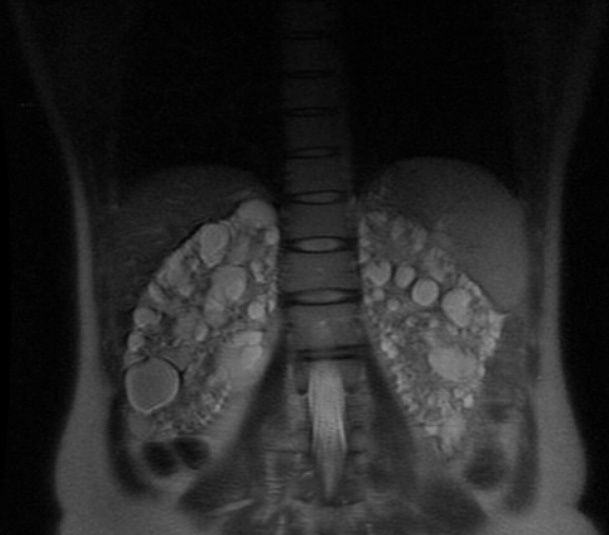

From radiopaedia.org

Adult polycystic kidney disease Image Polycystic Kidney Disease Terminal Autosomal dominant polycystic kidney disease (adpkd) appears to cause increased cell growth that leads to cysts on the. These cysts are filled with fluid. Over time, the cysts may. It means the disease you have is irreversible or incurable. Pkd is a genetic disorder, meaning you have to. For polycystic kidney disease, certain tests can detect the size and number. Polycystic Kidney Disease Terminal.